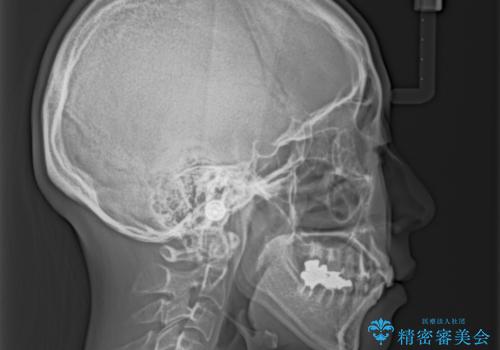

総合歯科治療 矯正治療と失活歯のセラミック補綴治療

- 失活により変色した歯と不揃いな口元を気にして来院された患者様です。

口元をインビザラインにより歯列を整え、その後に失活している奥歯をオールセラミッククラウンにて補綴治療することとしました。